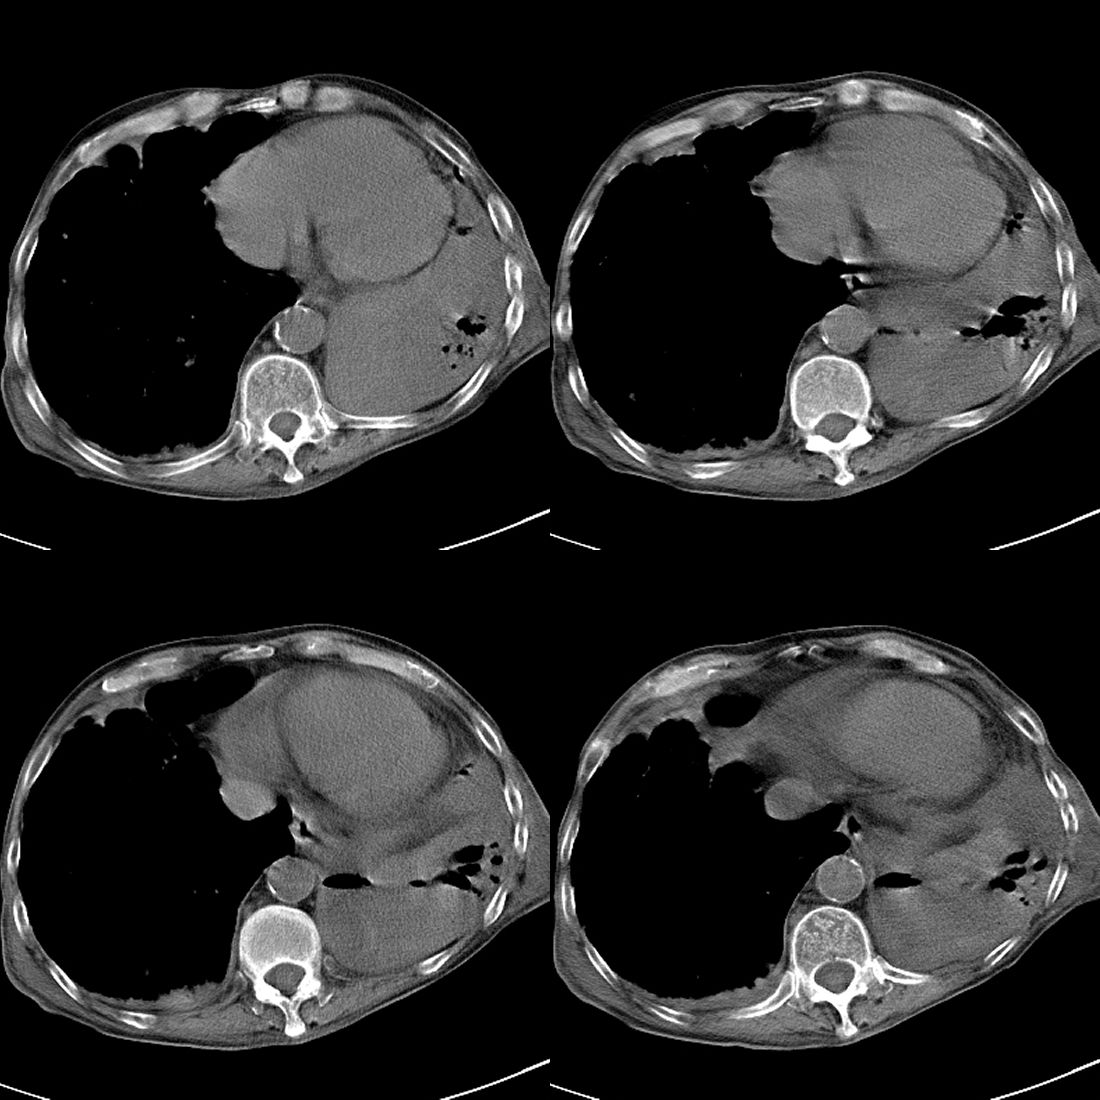

以下是引用liuyue在2008-11-30 6:01:00的发言:[br]双肺继发性肺结核;左侧包裹性积液;建议增强化或支气管镜检查除外左肺占位性病变.

以下是引用吴承学在2008-11-30 8:02:00的发言:[br]双肺继发性肺结核;左侧包裹性积液;建议增强化或支气管镜检查除外左肺占位性病变.[br]